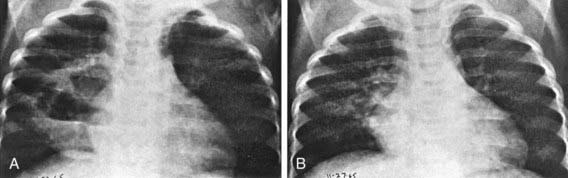

An abscess is usually a thick-walled lesion with a low-density center progressing to an air-fluid level. Abscesses should be distinguished from pneumatoceles, which often complicate severe bacterial pneumonias and are characterized by thin- and smooth-walled, localized air collections with or without air-fluid level (Fig. 394-3). Pneumatoceles often resolve spontaneously with the treatment of the specific cause of the pneumonia.

Figure 394-3 Appearance over a period of 5 days of a large multiloculated pneumonocele in a segment of alveolar consolidation. A, There is a large cavity with two air-fluid levels in a segment of alveolar pneumonia in the right upper lobe. B, Five days later, the cavity and most of the pneumonic consolidation have disappeared.

(From Silverman FN, Kuhn JP: Essentials of Caffrey’s pediatric x-ray diagnosis, Chicago, 1990, Year Book, p 303.)